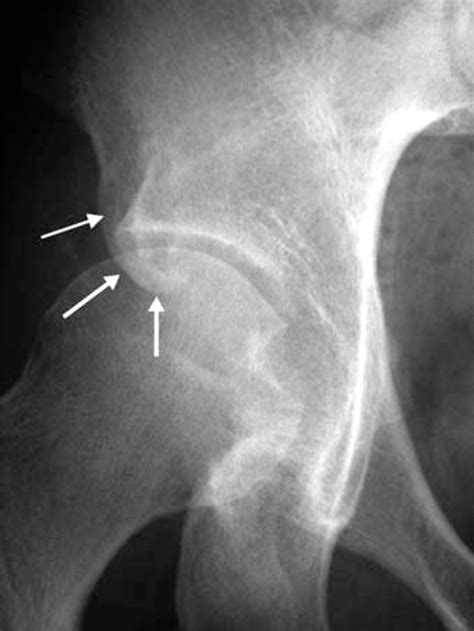

Furthermore, in sports medicine, the AIIS is often investigated when athletes report deep hip or groin pain. Because the rectus femoris attaches directly to this bone, repetitive kicking or sprinting movements can occasionally lead to an avulsion fracture, where a small piece of bone is pulled away by the muscle tendon.

Because the muscles attached to the Anterior Iliac Spine are responsible for high-force movements like running, jumping, and kicking, they are prone to specific injuries. Athletes, particularly adolescents whose bones are still developing, are at a higher risk for avulsion fractures. When the muscle contracts forcefully, the tendon can pull harder than the bone can withstand, leading to a fracture.

• Avulsion Fractures: More common in young athletes due to the vulnerability of growth plates.

1. X-ray: Excellent for identifying avulsion fractures or bone-related abnormalities.